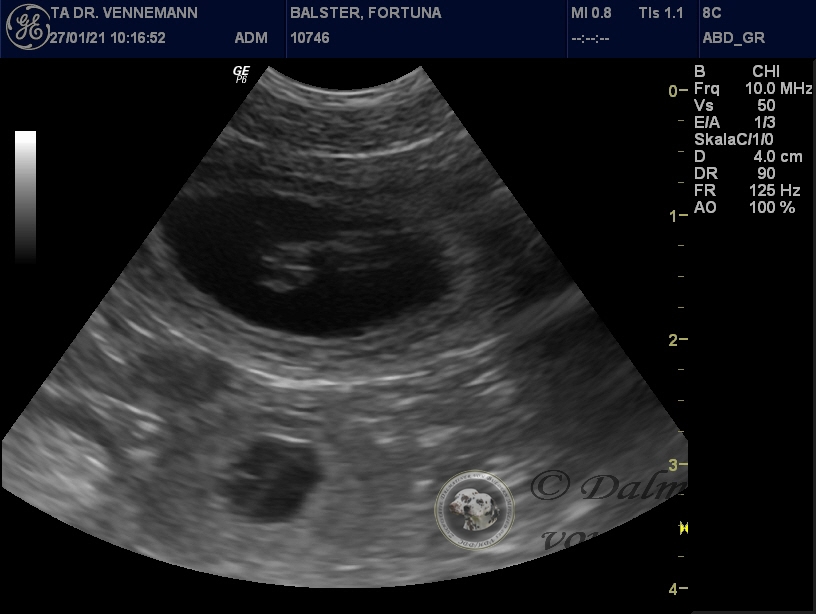

28.01.2021

Da sind sie nun...

...die ersten Bilder unserer kleinen Q-chen!

Der Ultraschall beim Tierarzt unseres Vertrauens hat uns Einblick in Selmas Bäuchlein gegeben. Deutlich sichtbar waren die schlagenden Herzchen der Winzlinge zu erkennen - immer wieder ein wunderbarer Anblick!